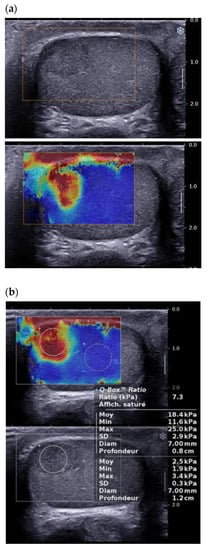

3.4. Elastography